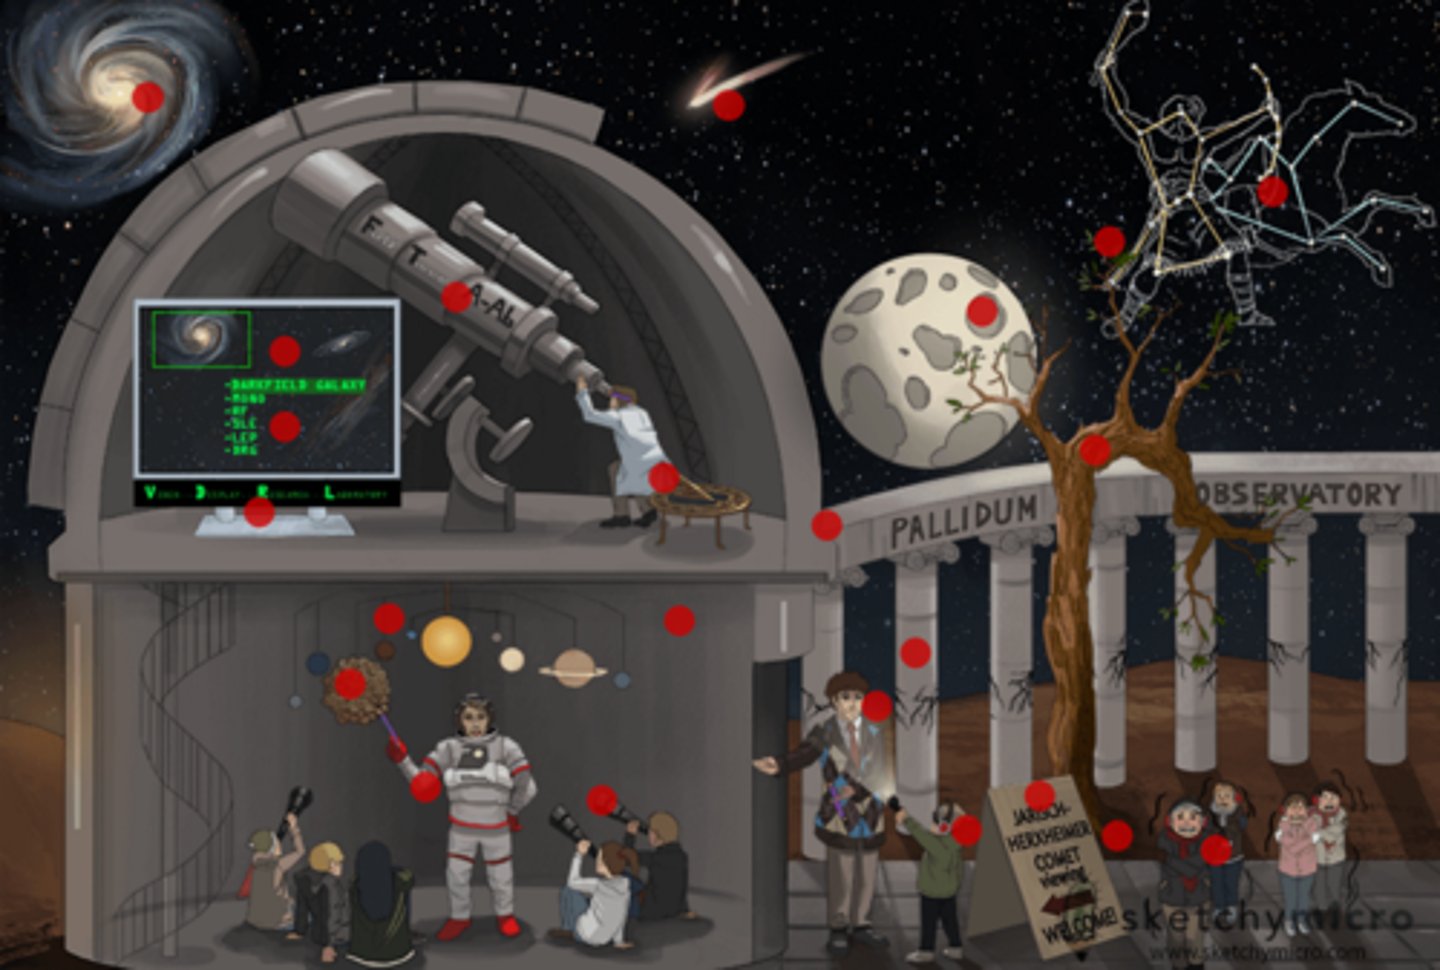

Fever, chills, headache, myalgia following antibiotic treatment for syphilis

Jarisch-Herxheimer reaction

(rapid lysis of spirochetes results in endotoxin release)